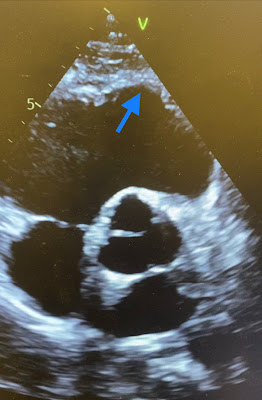

After the arrhythmia terminated the patient stabilized quickly and a bedside echocardiogram was obtained. The videos below show focused views of the right ventricle. The RV is dilated with decreased systolic performance, there is myocardial thinning and hypokinesis of the large areas of the RV, especially the apical regions and RVOT. RV EF on formal study was 34%. Right ventricular end diastolic volume (RVEDV) was significantly increased. Also noted was hypokinesis involving the LV in a non-coronary pattern. LVEF was preserved.

Below are focused views on the right ventricle (left frame) and RVOT (right frame). The videos show that both the RV and the outflow tract are significantly dilated. The RV myocardium shows regional myocardial thinning and aneurysms.

Below are still images with red arrows pointing to the dilated basal and apical regions of the RV. Circled in yellow is the midventricular region of the RV which shows less dilatation likely owing to restrain by the moderator band. Blue arrows point toward thinning of the myocardium both in the apical region of the RV and in the RVOT.